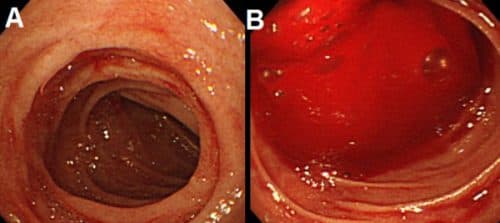

Viêm hang vị sung huyết là tình trạng niêm mạc hang vị dạ dày bị viêm, các mạch máu giãn nở do ứ máu nhiều. Bệnh cần được phát hiện và điều trị kịp thời, tránh tình trạng phát triển thành mạn tính. Viêm hang vị sung huyết là tình trạng niêm mạc hang vị […]